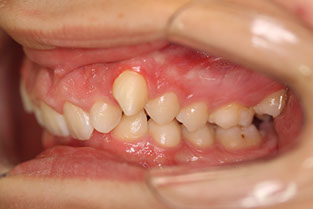

b.-Clase II, es cuando en la relación de la mordida las piezas inferiores se encuentran muy atrás con respecto a las superiores, los incisivos superiores podrían estar muy separados de los inferiores. Puede ser una característica solo de los dientes o de toda la cara, en este ultimo caso tenemos a las personas cuyo mentón se encuentra muy atrás.